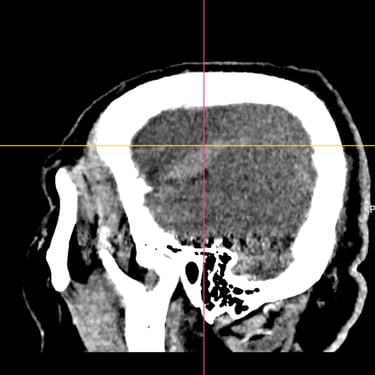

El hematoma subdural subagudo se caracteriza por la acumulación progresiva de sangre entre la duramadre y la superficie cerebral, generalmente posterior a un traumatismo craneal. Esta condición puede generar síntomas como dolor de cabeza persistente, confusión, debilidad en extremidades o alteración del estado de conciencia. El tratamiento quirúrgico consiste en la evacuación del hematoma mediante burr hole ampliado, técnica que permite realizar un orificio en el cráneo para drenar el contenido hemático y descomprimir el cerebro. Este procedimiento ayuda a disminuir la presión intracraneal, mejorar los síntomas neurológicos y prevenir complicaciones asociadas a la compresión cerebral.